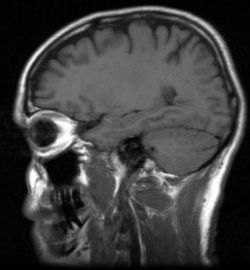

Následky ochorení mozgu sa v porovnaní s minulosťou veľmi nezmenili

Dnes je možné vzniku mnohých ochorení mozgu zabrániť, je možné zmierniť ich priebeh, ale pokiaľ ide o následky a priebeh vážnych mozgových príhod, v porovnaní s minulosťou sa pri ochoreniach mozgu až tak veľa nezmenilo. Pre TASR to uviedol neurológ Marián Kondáš z I. Neurologickej kliniky FNsP v Bratislave.

Sekundárne bolesti hlavy môžu byť spôsobené nádormi, krvácaním do mozgu, subarachnoidálnym krvácaním – teda krvácaním pod mozgové obaly. V týchto prípadoch je podľa neurológa potrebné u pacienta pomocou presnej diagnostiky, napr. CT vyšetrením alebo magnetickou rezonanciou čo najskôr zistiť príčinu tejto bolesti. Kondáš skonštatoval, že výskyt infekčných ochorení mozgu je podmienený aj stavom imunitného systému. "Napríklad meningoková meningitída, ktorá bola častá pri zníženej imunite vo vojenských kolektívoch, má dnes menej častý výskyt," uviedol. Zároveň však upozornil, že aj z bežných vírusov ako napr. herpes môže vzniknúť závažná infekcia, herpetická encefalitída – zápal mozgu. Medzi ďalšie infekčné ochorenia patrí napr. herpes zoster, teda pásový opar, ktorý spôsobuje silné bolesti v priebehu nervových koreňov; patrí sem borelióza prenášaná kliešťami.

V súčasnosti patria medzi závažné postihnutia mozgu úrazy hlavy. Ich výskyt je podmienený aj rozvojom motorizmu. Na Slovensku na cestách zomiera okolo 600 ľudí ročne. Poranenia hlavy spôsobujú pády, údery, nárazy, úrazy pri športe, ktoré môžu najmä v staršom veku spôsobovať závažné komplikácie. Úrazy hlavy sa podľa Kondáša delia na komócie a kontúzie. Komócia je vlastne otras mozgu. "Tento termín sa dnes už používa zriedkavejšie, pretože CT vyšetrenia a vyšetrenia magnetickou rezonanciou umožňujú oveľa presnejšiu charakteristiku toho, čo sa pri úraze hlavy stalo. Prístroje dokážu zaznamenať, či došlo na mozgu aj k morfologickým zmenám alebo či to bol len tzv. funkčný otras mozgu," zhodnotil odborník. Podľa neho je pri traume hlavy vždy dôležité, či pri nej vznikla porucha vedomia, ktorá mohla trvať často aj niekoľko minút. Po úrazoch hlavy môže vzniknúť porucha pamäti, ktorá sa môže týkať rôzneho obdobia pred úrazom alebo po úraze.